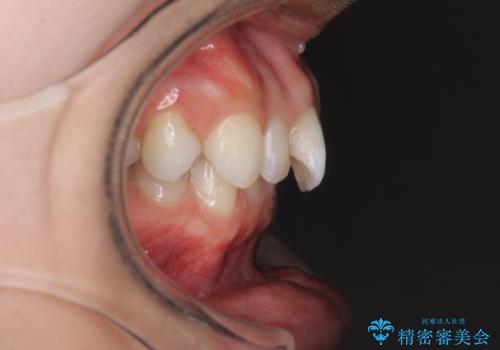

深い咬み合わせと奥歯のむし歯 総合歯科治療

- 奥歯の虫歯と前歯のデコボコや突出感を気にして来院された患者様です。

上顎歯列が、下顎に対して前方にありましたが、口元に出っ歯の印象がなかったため、親知らずを抜歯した上で、上顎歯列全体を後方に移動させることとしました。